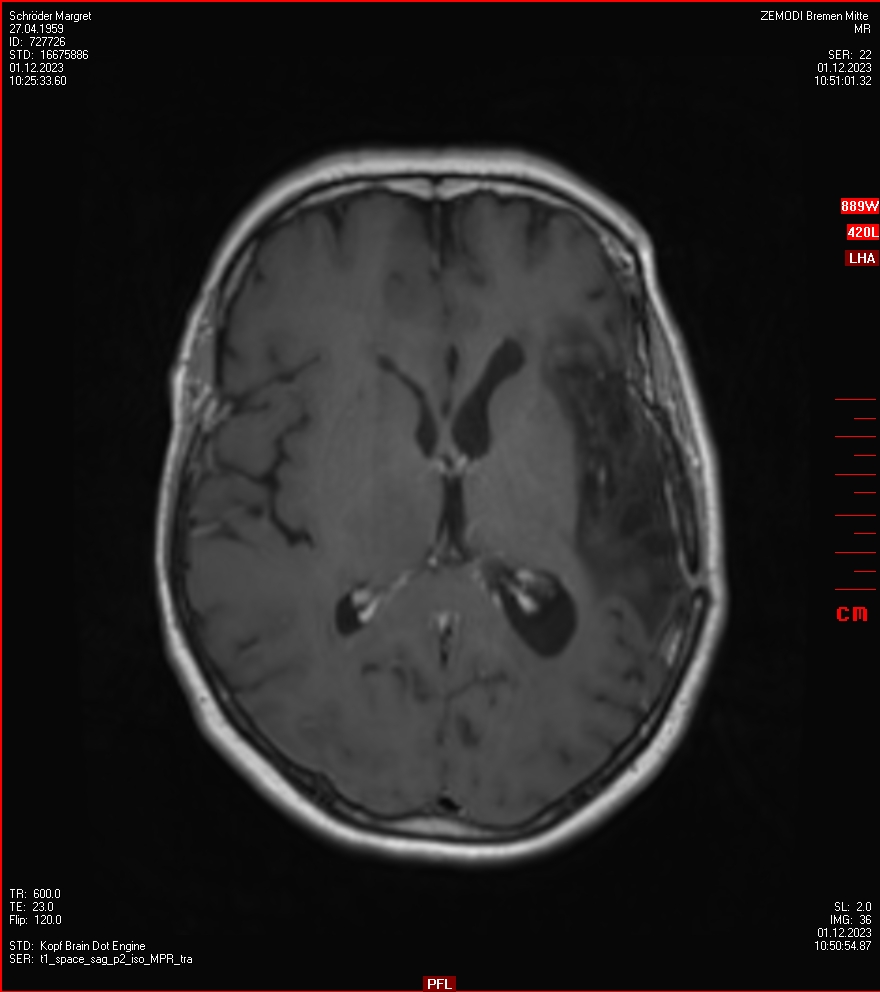

Zum Vergleich nun auch die Bilder vom 1.12.2023:

Ich denke, in den letzen 12 Monaten sind da ein paar Rezidive gewachsen,  vor 12 Monaten waren sie auch schon zu erkennen - vorher noch nicht. Nun hoffe ich auf den Rat des Spezialisten. Hoffendlich kann man etwas machen.